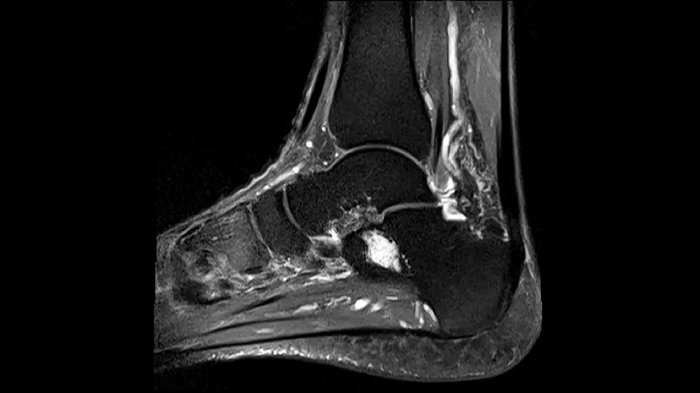

Ankle

Ankle - PD TSE FatSat

Even in demanding anatomies such as ankle with Contour S Coil, achieve optimal image quality.

• Contour S Coil

80 cm bore MAGNETOM Free.Max

Image Courtesy: University Hospital Erlangen, Germany | Image-ID: 4aaaa0381